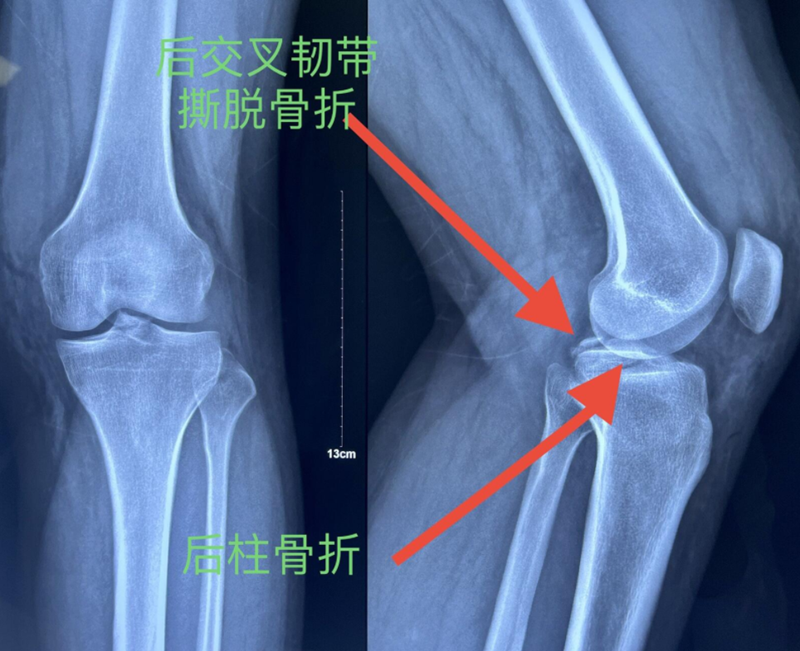

x男,30岁,体重100kg,在五楼擦玻璃时坠落到四楼致伤2天。

诊断:左胫骨平台后柱骨折,后交叉韧带撕脱骨折,左踝关节pilon骨折3型。

图7 前交叉韧带撕脱骨折与平台后柱骨折